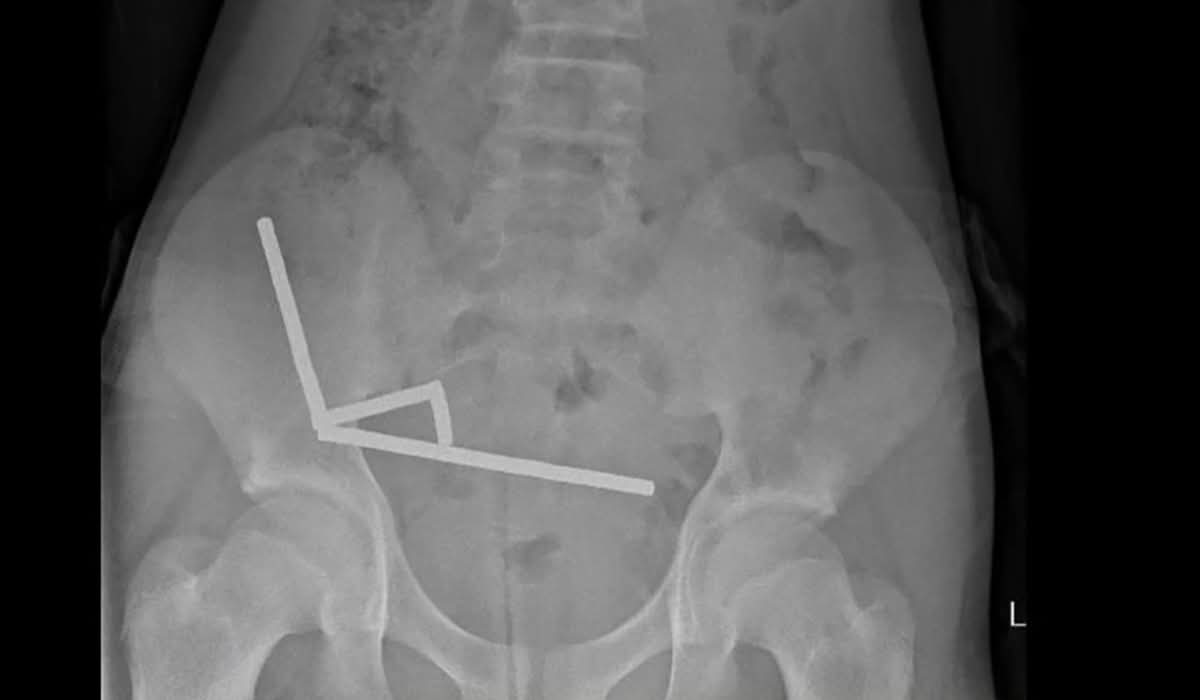

Un băiat de 13 ani din Noua Zeelandă a fost internat în spital după ce a înghițit între 80 și 100 de magneți puternici. Acesta a stat aproape o săptămână fără să ceară ajutor medical, în ciuda simptomelor îngrijorătoare. Situația a atras atenția autorităților sanitare locale.

În urma examinării și intervenției chirurgicale, medicii au fost nevoiți să îndepărteze o parte a intestinului pacientului, afectată grav de corpul străin. Intervenția s-a impus pentru a preveni complicații majore care îi puneau viața în pericol. În acest caz, timpul a jucat un rol crucial.